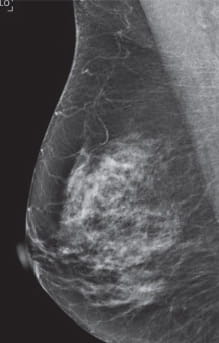

Heterogeneously dense stage 1 breast cancer mammogram

Heterogeneously dense stage 1 breast cancer mammogram- "By the time the cancer would have been picked up by a mammogram, it could have been stage two or three patients with heterogeneously or extremely dense breast tissue, with a negative5 Facts to Know Breast density is determined through a woman's mammogram and described as one of four categories depending on the amount of breast tissue in comparison to fat in the breast;

Imaging Findings A 2dimensional (2D) mammogram revealed heterogeneously dense breast tissue without focal masses or asymmetries and without changesThis means that you have moderately dense tissue, which is common and not a cause for concern Sometimes, dense tissue can make it difficult to accurately read a mammogram#2 Increased Breast Cancer risk • Women with heterogeneously dense breasts & extremely dense breast tissue may have higher risk of breast cancer compared to women with lower density breasts • Extremely Dense vs Fatty – 46x • Risk of breast cancer in dense vs scattered density is about 1

In clinical practice in the United States, Breast Imaging Reporting and Data System (BIRADS) breast density categories are used in mammographic reports to indicate the degree of mammographic breast density a) The breasts are almost entirely fatty, b) There are scattered areas of fibroglandular density, c) The breasts are heterogeneously dense, which may obscure small masses, and d) The breasts are extremely denseStage breast cancer within weeks of a 'normal' mammogram It was at this time that I learned that I had dense breast tissue and wasn't aware of its significance as 1) Mammography misses every other cancer in dense breasts as cancer appears white on a mammogram and dense tissue is whitethus there is no contrast to see the cancer and 2) the Stage T1c, N0, M0 stage 1 left breast cancer IMAGING FINDINGS A 2dimensional (2D) mammogram revealed heterogeneously dense breast tissue without focal masses or asymmetries and without changes when compared to earlier mammograms (Figure 1) A 3dimensional (3D) mammogram revealed an area of architectural distortion in the lateral aspect